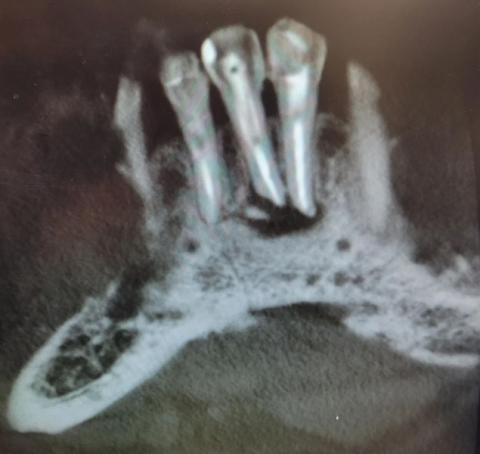

The X-ray image shows severe bone loss and dark radiolucent areas around the roots of multiple teeth. The surrounding jawbone appears irregular, hollowed, and damaged, which strongly indicates advanced infection spreading through the bone.

The tooth roots are clearly visible with loss of normal bone support, a serious sign that the infection is no longer limited to the gums.

This X-ray shows a severe dental abscess with jawbone involvement, a critical condition requiring urgent professional treatment. Early intervention can stop the infection and preserve remaining bone structure.